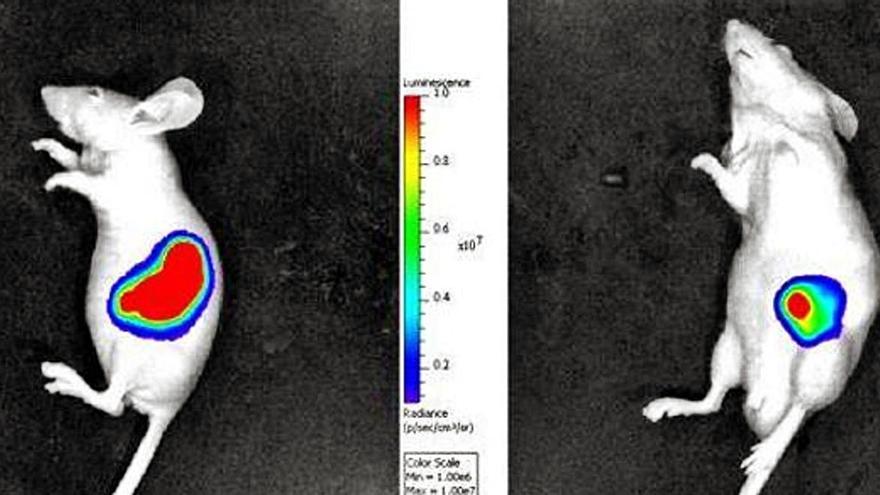

Empleando modelos animales de pez y roedor, los investigadores han comprobado que, al bloquear la fascina1 con imipramina, estas células tumorales se vuelven menos invasoras y menos metastásicas.

Los estudios posteriores realizados en modelos de invasión en ratón han confirmado la actividad antitumoral de este fármaco, que empezará a probarse en ensayos clínicos en pacientes oncológicos de la Región de Murcia, gracias a los fondos obtenidos a través de una convocatoria del Instituto de Salud Carlos III.